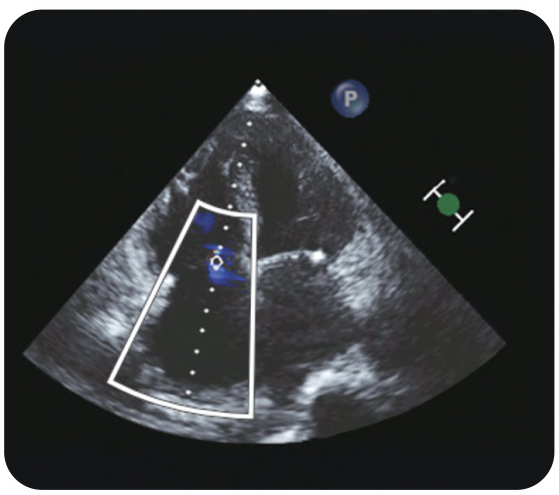

Case 8 -Young Boy Presenting with Breathlessness

Click here to view